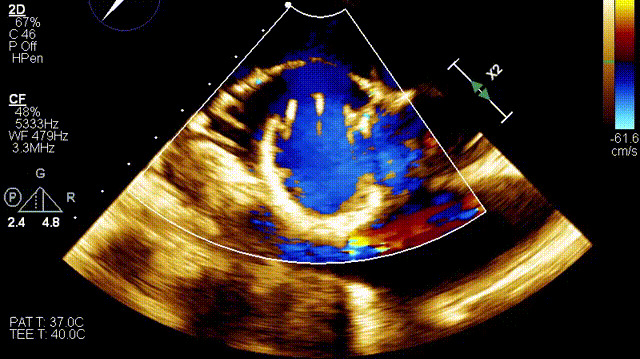

術(shù)后DSA

術(shù)后超聲